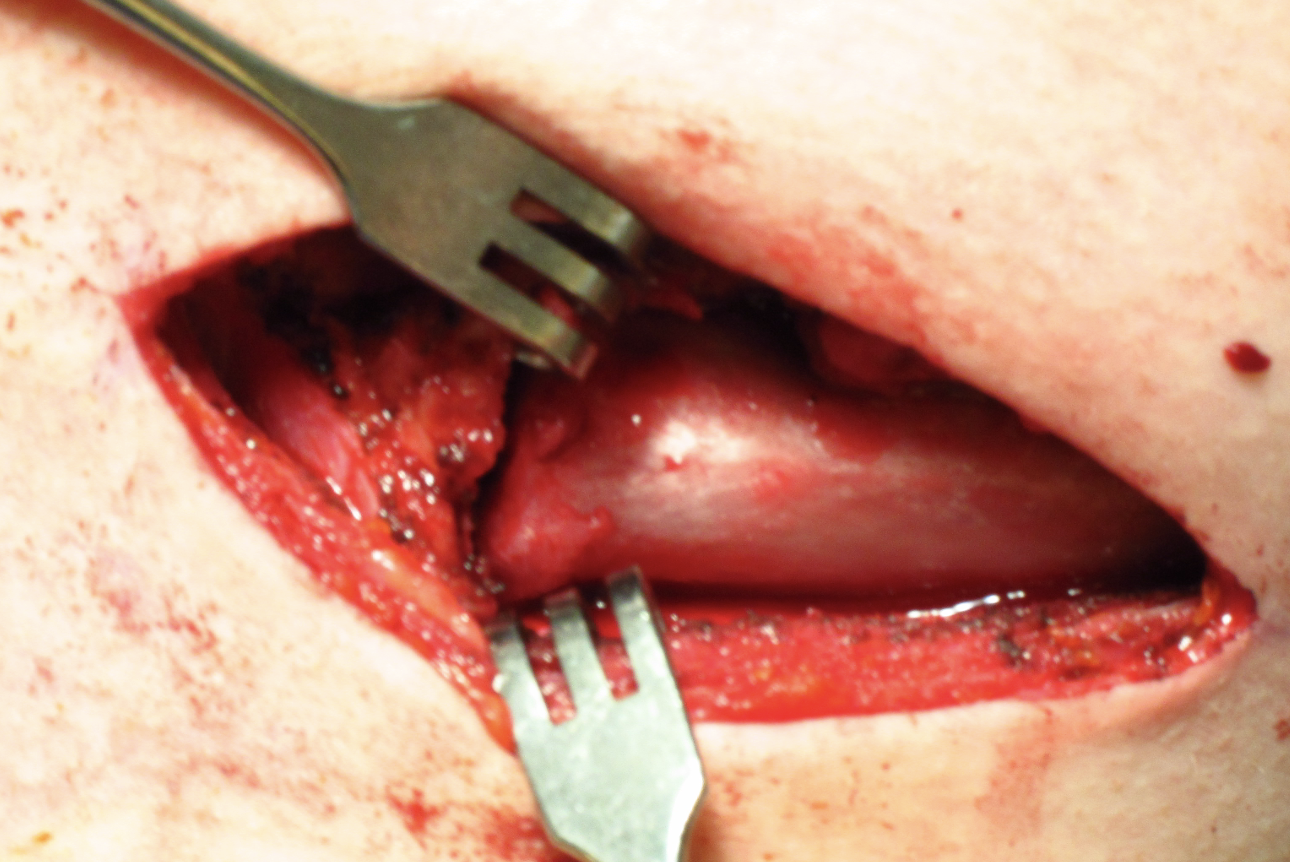

2. Open reduction

Performed under GA in operating room

- chest surgeon available

- potential vascular / airway catastrophe associated with injuries to the mediastinum

- thorough vascular imaging pre-operatively

Technique

Vumedi posterior SCJ reduction and hamstring allograft stabilization video

Vumedi chronic posterior SCJ reduction and reconstruction video

Open reduction of acute posterior sternoclavicular joint dislocation

Drill holes in manubrium and medial clavicle

Figure of 8 suture fixation